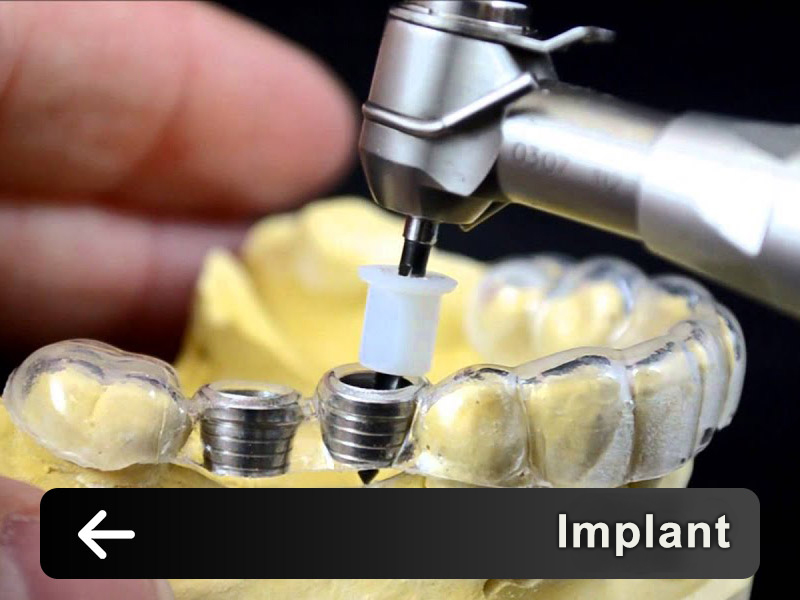

services

The set of digital laboratories of Ganjineh Teb Arman Company provides a complete set of stages from the treatment plan to the manufacture of therapeutic aids and prosthetics by using the skills of experienced technicians and expert dentists..Login and register in the system